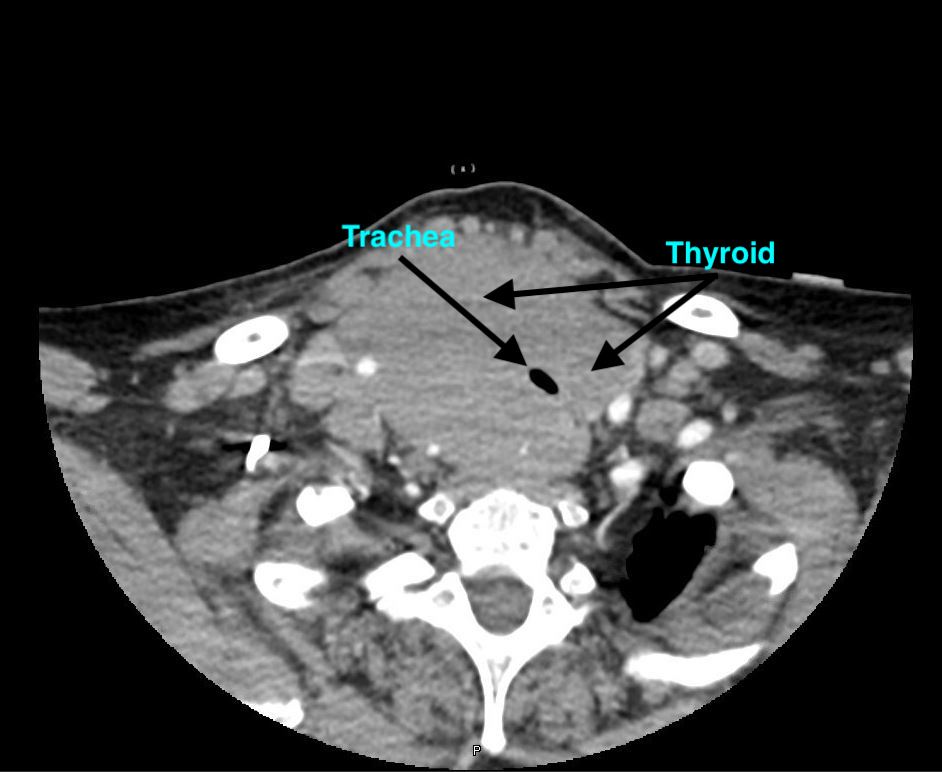

A CT scan of the neck was performed to evaluate the patency of the patient’s airway, and the corresponding images showed a hypodense lesion, which represented the air in trachea, completely surrounded by high-density tissue consistent with thyroid tissue—a radiologic sign that is commonly known as the doughnut sign (Figures).

The subsequent pathology results from the hemithyroidectomy were consistent with diffuse large B-cell lymphoma. The annual incidence of this disease is estimated to be 2.1 per million persons, with a 4 to 1 female predominance.3 The only known risk factor for this condition is preexisting chronic autoimmune thyroiditis. This patient’s case is a very typical presentation of thyroid lymphoma; however, the CT finding of thyroid tissue encasing the trachea is pathognomonic for this condition. She was started on the R-CHOP (rituximab, cyclophosphamide, doxorubicin, vincristine, and prednisone) chemotherapy regimen and has been responsive to therapy.